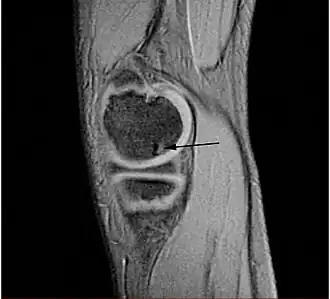

Osteocondritis disecante

![]() Lesión típica de osteocondritis disecante en la cabeza del fémur, causada por una necrosis avascular del tejido subcondral. | ||

Osteocondritis disecante (a menudo abreviado TOC o DO) es un trastorno común en el que se forman grietas en el cartílago articular y el hueso subyacente subcondral. El TOC es una complicación de la necrosis avascular que se producen en el hueso subcondral.[1] Esta necrosis avascular priva de sangre a los huesos; el tejido afectado muere y se reabsorbe. El hueso subcondral se pierde, el cartílago articular anterior se separa del hueso y es más propenso a los daños, como la fragmentación (disección) de los cartílagos y huesos, y la libre circulación de estos fragmentos osteocondrales en el espacio articular, causando más dolor y daño.[2][3][4]

La osteocondritis disecante se distingue de "desgaste" artritis degenerativa, que es principalmente un problema de superficie articular. En cambio, el TOC es un problema del hueso subcondral subyacente, que secundariamente pueden afectar el cartílago articular. Si no se trata, el TOC puede conducir al desarrollo de la artritis degenerativa secundaria a la incongruencia articular y desgaste anormal.[26]

TOC se produce cuando un pedazo suelto de hueso o cartílago parcialmente (o totalmente) se separa del extremo del hueso, a menudo debido a una pérdida del suministro sanguíneo (osteonecrosis) y descalcificación de la matriz ósea trabecular. El pedazo suelto puede quedarse en el lugar o la diapositiva alrededor, haciendo que la articulación rígida e inestable. TOC en los seres humanos con mayor frecuencia afecta las rodillas,[27] los tobillos y codo, pero puede afectar cualquier articulación.[28]